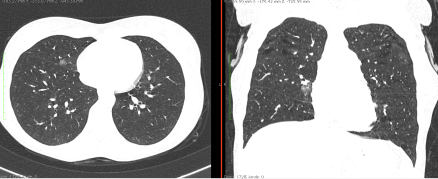

КТ имеет высокую чувствительность в выявлении изменений в легких, характерных для COVID-19. Применение КТ целесообразно для первичной оценки состояния ОГК у пациентов с тяжелыми прогрессирующими формами заболевания, а также для дифференциальной диагностики выявленных изменений и оценки динамики процесса. КТ позволяет выявить характерные изменения в легких у пациентов с COVID-19 еще до появления положительных лабораторных тестов на инфекцию с помощью МАНК. В то же время, КТ выявляет изменения легких у значительного числа пациентов с бессимптомной и легкой формами заболевания, которым не требуется госпитализация. Результаты КТ в этих случаях не влияют на тактику лечения и прогноз заболевания при наличии лабораторного подтверждения COVID-19. Поэтому массовое применение КТ для скрининга асимптомных и легких форм болезни не рекомендуется.

4. Все выявляемые при лучевых исследованиях признаки, включая КТ-симптомы, не являются специфичными для какого-либо вида инфекции и не позволяют установить этиологический диагноз. Вне клинической (эпидемической) ситуации они не позволяют отнести выявленные изменения к пневмонии COVID-19 и дифференцировать их с другими пневмониями и невоспалительными заболеваниями. Данные лучевого исследования не заменяют результаты обследования на РНК SARS-CoV-2. Отсутствие изменений при КТ не исключают наличие COVID-19 и возможность развития пневмонии после проведения исследования.